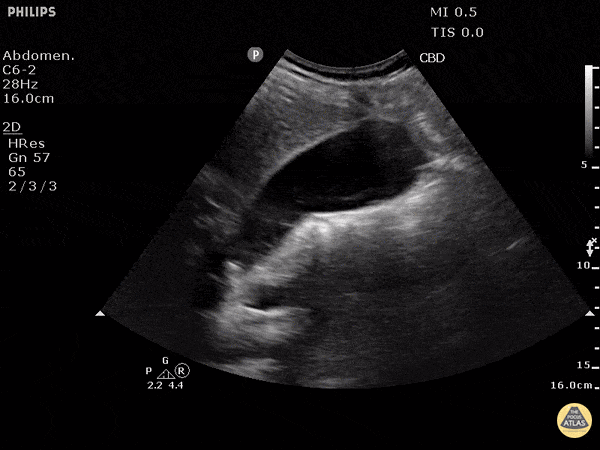

Biliary - Cholelithiasis with Many Stones

This non-inflamed gallbladder contains many stones. The stones are hyperechoic with posterior shadowing. The gallbladder wall is not thickened, there is no pericholecystic fluid, and no sonographic Murphy's sign, thus cholecystitis is unlikely. Justin Bowra MBBS, FACEM, CCPU Emergency Physician, RNSH et al. (Dr. Ken Lee)